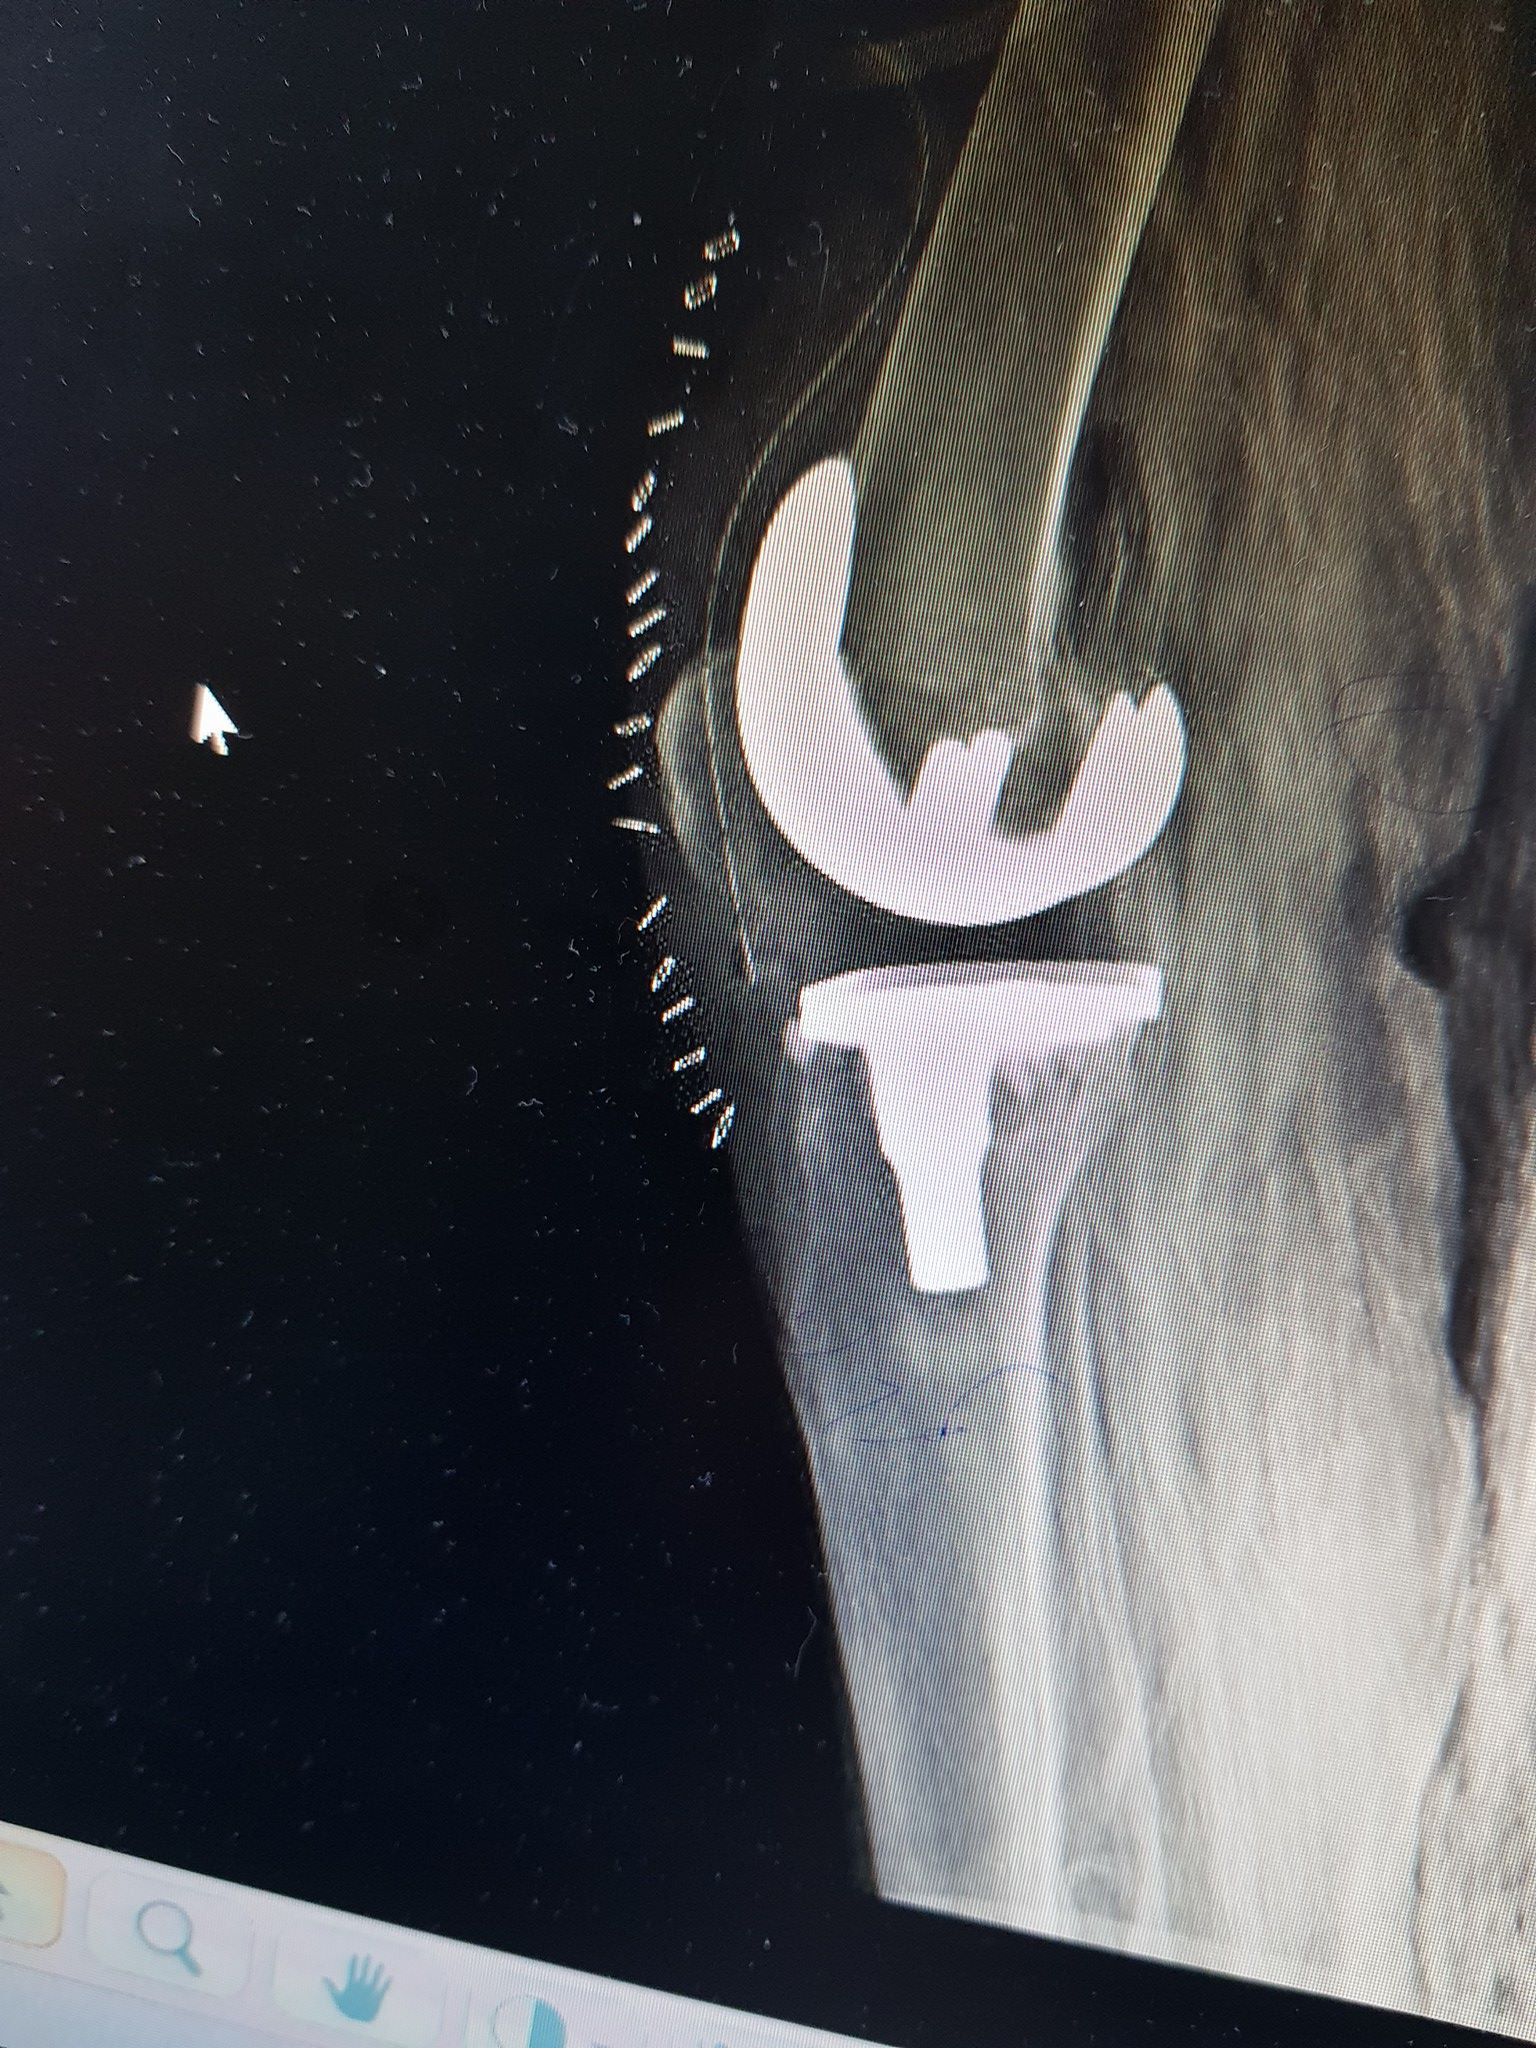

زراعة المفاصل الصناعية ورك و

كافة انواع الكسور وعلاجها